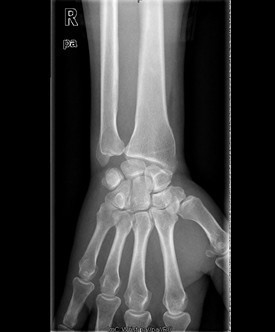

患者男,60岁,因“右腕部疼痛5月,右小指屈曲障碍20天”入院。入院前5月,患者无明显诱因情况下出现右侧腕部尺侧酸痛不适,未就诊治疗。左小指伸曲正常;入院前20天,患者出现右小指屈曲障碍,无小指指麻木,遂来我院治疗,门诊以“左小指深浅屈肌腱迟发性断裂”收入院。

查体:右侧小指伸直位,不能屈曲。右侧腕部尺侧可触及一质韧包块。右小指感觉正常,末梢循环正常。右小指不能主动屈曲掌指关节及中节、末节手指;伸指正常,余手指活动正常。 辅查:彩超示右腕包块处肌腱周围粘稠积液伴滑膜增厚。